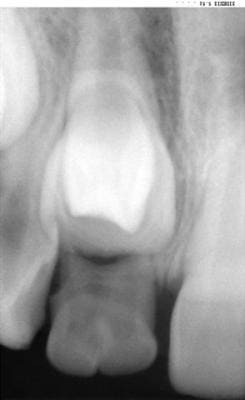

Lacand ayant des petits problemes de connexion internet, il m'a permis en son nom de diffuser les 3 images, qu'il vous commentera par la suite.

bonjour,

si je peux me permetre

dens in dente(odontome invaginé)

le pertuis palatin=la dent invaginée

dès que la dent sera sur l'arcade,obturer au composite ou autre mais étanche(!!!) le pertuis palatin qui est une porte d'entrée jusqu'à la pulpe

et le traitement canalaire d'une telle dent est quasi infaisable avec de bons résultats à long terme

compte tenu de l'age,faire de la place et tracter(avis odf)

Mon t45, je ne peux rien dire car la primeur en revient à lacand qui a super bien fait de choisir une autre incidence (profil). Et je suis vachement content pour sa petite patiente. Regardez bien!

surnuméraire en superposition?

il me semble voir comme adhoc,une racine separee et une petite couronne en arriere de la 11

En fait je viens de mettre les BK avec un sectionnel en attente de la pose d'un coil spring.Car avant de faire ma télé de profil je pensais préparer une place suffisante pour laisser évoluer spontanément la 11 et dans le cas où le manque de place ne serait pas l'obstacle je l'adresserai chez un ORL avec qui je travaille afin de m'extraire ce qui pourrait être un odontome ou une dent de lait surnuméraire( ou tout autre,on ne vas pas épiloguer sur le terme).En dernier recours je tenterai la traction et en dernier recours seulement car d'une part celà n'est pas sans risque et d'autre part il faut tenir compte de l'âge de la patiente( 8 ans) et de la position des parents face à tout cet arsenal thérapeutique qui nous paraît, à nous praticiens, simple parceque dans nos cabinets ces pratiques sont courantes mais pour l'enfant et pour les parents le ressenti n'est pas le même.

Je ferais pareil que toi, lacand, une fois maintenant notre diagnostic différentiel tres heureusement résolu. Peut etre que ca a changé, mais on m'avait appris qu'il ne fallait "s'affoler" (ici dans le sens d'une traction) que 2 ans et demi à 3 ans apres la date normale d'erruption. Et 8 ans, ca te laisse peinardos 1 an et demi.

Et comme les intervenants ont cité aussi tres justement le bloquage , je pense que la manoeuvre chirurgicale d'extraction de la dent surnuméraire va ...bé... débloquer la situation. Le chirurgien pourra meme dégager un peu plus d'os pour accompagner une erruption qu'on espère tous spontanée.

je pense vu l'age de l'enfant que si tu veux avoir une chance que la 11 fasse une éruption normale tu ne dois pas tergiverser et pratiquer l'avulsion chirurgicale de la surnuméraire sans plus attendre.

c'est du temps perdu,elle ne va pas evoluer spontanement,d'accord avec jazz pour intervenir le plus tot possible avec extraction de l'odontome

L'extraction de la dent surnuméraire rapidement oui, mais la traction immédiate certainement pas car si tu avais bien observé la télé de profil, tu aurais remarqué que la 11 n'a pas fini la formation de sa racine.Je pense que le plus sage c'est d'attendre trois ou quatre mois avant de refaire une autre télé et prendre une décision définitive.